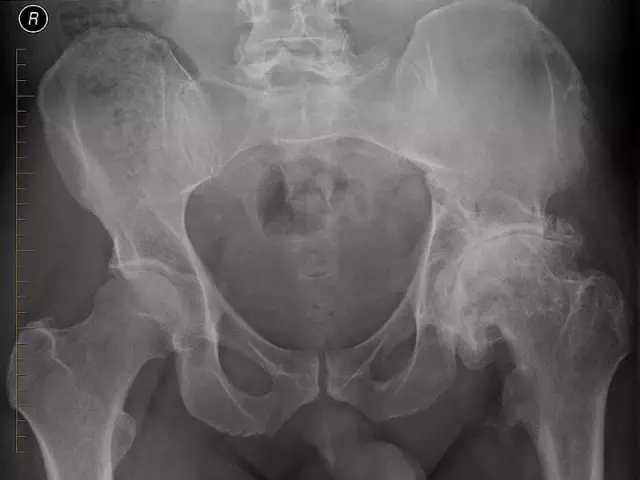

Все операции по эндопротезированию тазобедренного сустава с революционной техникой ASI (межмышечная передняя часть спины) у пациентов с высоким индексом массы тела с большим успехом выполняются в клинике Великих Суставов Афинского медицинского центра директором отделения, Иоаннис Царуш и его команда.

Революционная методика минимальной инвазивности ASI идеально подходит для пациентов с ожирением и избыточным весом, так как требует очень маленького разреза (всего 6-7 сантиметров в длину) на передней поверхности бедра, где накопление жира минимально.

Таким образом, предоперационная потеря веса не требуется, и тотальная артропластика может, если есть доказательства, быть немедленной. Поражение мягких частиц минимально, так как избегается поперечное сечение мышц и сухожилий, а продолжительность операции составляет около полутора часов. Послеоперационная боль сводится к минимуму, и сустав, благодаря защите мягких частиц, стабилен с первого дня. Это означает, что пациент может сразу встать и ходить. Продолжительность госпитализации ограничена тремя-четырьмя днями.

«Классическая эндопротезирование тазобедренного сустава с разрезами в боковых или задних бедрах, а также их более новые и более продвинутые формы имеют значительные трудности у пациентов с ожирением / избыточным весом, поскольку накопление жира в ягодицах затрудняет доступ к бедру, существует необходимость в больших разрезах и значительном поражении мягких частиц, главным образом мышц, что вызывает более сильное кровотечение, сильную боль и очень медленное выздоровление. По вышеуказанным причинам операция на бедре обычно рекомендует (Anterior Supine Intermuscular) является методом выбора для пациентов с ожирением / избыточным весом, и мы очень гордимся тем, что можем предложить это решение в Греции и медицинском центре Афин ", сказал доктор Иоаннис Царушас, директор Клиники крупных суставов Медицинского центра Афин.